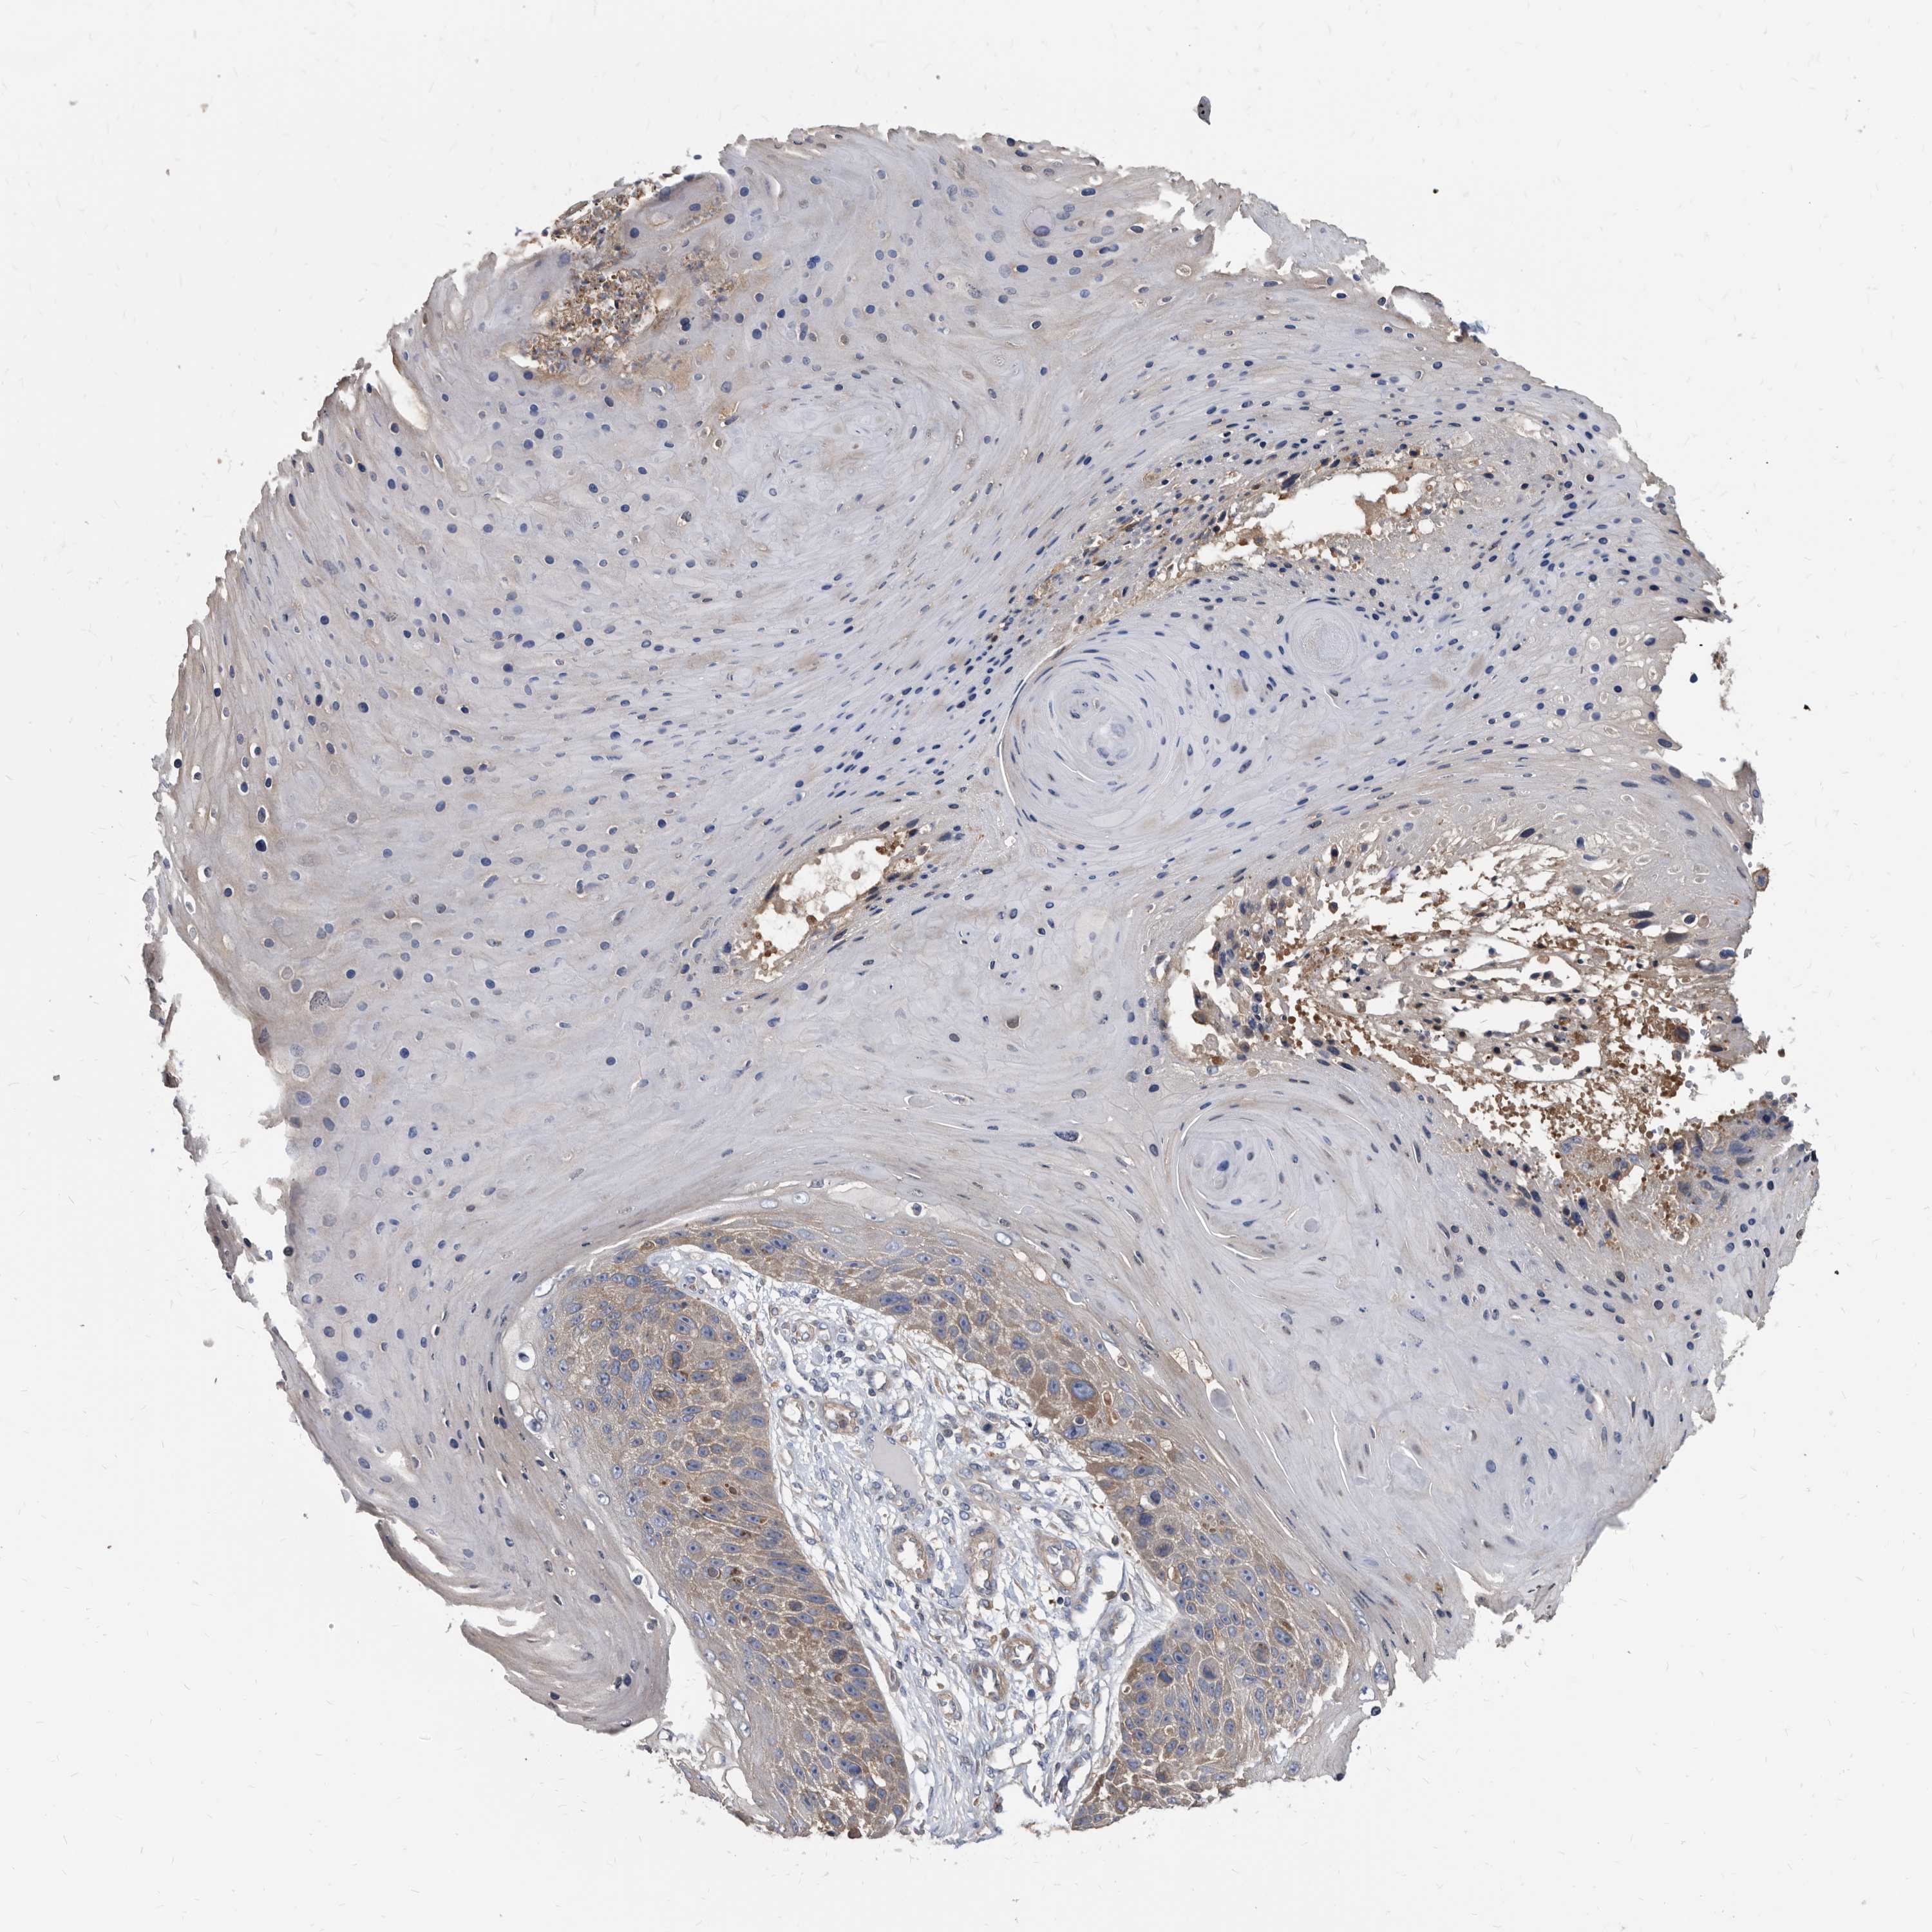

SKIN CANCER - Protein expressioni

A mouse-over function shows sample information and annotation data. Click on an image to view it in a full screen mode. Samples can be filtered based on level of antibody staining by selecting one or several of the following categories: high, medium, low and not detected. The assay and annotation is described here.

Each image is clickable and will lead to virtual microscopy that enables deeper exploration of all samples and also displays staining intensity scores, fraction scores and subcellular localization as well as patient and tissue information for each sample.

Antibody HPA029700

Antibody HPA029701

Antibody HPA029702

Antibody HPA029703

Staining

High

Medium

Low

Not detected

Intensity

Strong

Moderate

Weak

Negative

Quantity

>75%

75%-25%

<25%

None

Location

Nuclear

Cytoplasmic/membranous

Cytoplasmic/membranous,nuclear

Basal cell carcinoma

Squamous cell carcinoma, NOS

Squamous cell carcinoma, metastatic, NOS